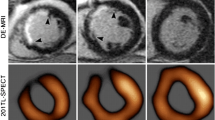

Figure 3 shows a mid-ventricular short axis views of both hearts. The RV of the healthy heart is thicker than the RV of the ARVC heart (Fig. 3a,d) with a low amount of epicardial fat surrounding the RV, and without fat infiltration in the septum (Fig. 3b,e). Moreover, MTR of the healthy heart (Fig. 3f) denotes an absence of bright signal in the myocardium, in contrast to ARVC heart (Fig. 3c).

Short axis view of the ARVC and healthy hearts. Short axis view of the ARVC heart (top) and the healthy heart (bottom). An IDEAL first echo (a,d), proton density fat fraction map (PDFF) (b,e) and MTR contrast (c,f) of both the hearts respectively are shown. The healthy heart presents some residual formalin in the RV, leading to some susceptibility artefacts on the PDFF (dark green arrow).

Figure 4 presents a detailed analysis of the water-fat and MT imaging in the slice presented in Fig. 2. Figure 4a illustrates the slice location on the 3D rendering of the PDFF. Figure 4b depicts the image with the shortest TE in the IDEAL sequence. Fat appears as a hypointense signal surrounding the ventricles, with clear delineation from the myocardium in the left ventricle. The RV free wall is composed of only a thin layer (3–10 mm) of fatty tissue with little or no apparent myocardium. The red dashed rectangle is focused on the interventricular septum. Within this rectangle, there is a susceptibility artefact (dark green arrow) due to a remaining air bubble trapped in the right side of the septum during sample fixation. Figures 4c–g show cropped views of the red dashed rectangle displayed in Fig. 4b. Figures 4c and 3d show water and fat images resulting from hierarchical IDEAL post-processing. Pink arrows in Fig. 4d show fat infiltrations into the septum, which are also observed on the PDFF map (Fig. 4e, displayed without threshold). These adipose tissues are present in smaller quantities (40–70% of fat) than the fat surrounding the ventricle (> 70%). Figure 4f shows the MT ratio map of the same region. A high intensity signal (MTR > 75%) is observed in the septum (purple arrows). Figure 4g shows superimposition of the PDFF (with a 40% threshold) over the MTR image. Fatty infiltrations are observed in the vicinity of the region with a high MTR. This overlaid image indicates that the hyperintense signal in the MTR (purple arrows) does not fully correspond to the presence of fat in some small areas (pink arrows).

IDEAL outputs and MTR of the ARVC heart. Short axis view of the ARVC heart. A 3D rendering (a) showing water in grey, fat in white and the position of the slice in red, IDEAL first echo (b), proton density fat fraction map (PDFF) (e) calculated from water (c) and fat (d) images and MTR contrast (f) are shown. An overlay of the proton density fat fraction map on the MTR is displayed (g). All images show an artefact due to an air bubble trapped during the sample fixation (dark green arrow). (d) and (e) display fat infiltrations (dark green arrows) and (f) shows the presence of fibrosis (purple arrows).